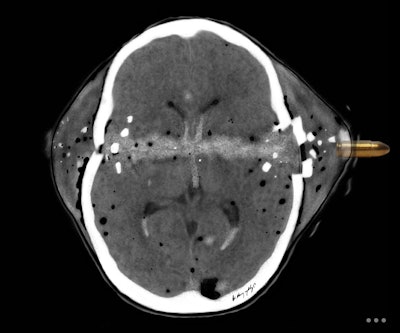

Art and radiology may seem like very different fields, but they can intersect in intriguing ways, particularly in medical imaging and the visualization of complex clinical data. Dr. Harun Yildiz has a keen interest in pediatric radiology, including ultrasound. All images provided by Dr. Harun Yildiz.

Dr. Harun Yildiz has a keen interest in pediatric radiology, including ultrasound. All images provided by Dr. Harun Yildiz.

Conceptually, I think it is possible to define the term “radiological illustration” as an emerging discipline that transforms medical imaging data into an aesthetic and didactic narrative. I emphasize that with the motto “pixel by pixel handmade.” I am trying to open a “new path” for the use of visual communication in medical education by trying to combine scientific accuracy in radiological terms with artistic creativity. With this statement, I am trying to express that instead of modifying radiological images, I draw each pixel by hand using technological tools and create a new visual that is both artistically and scientifically original, while remaining faithful to radiological principles.

It’s important to note that radiological illustration should not be confused with medical illustration. The former has yet to be systematically defined in the literature. I believe it deserves recognition as a distinct sub-branch within the broader medical illustration domain.